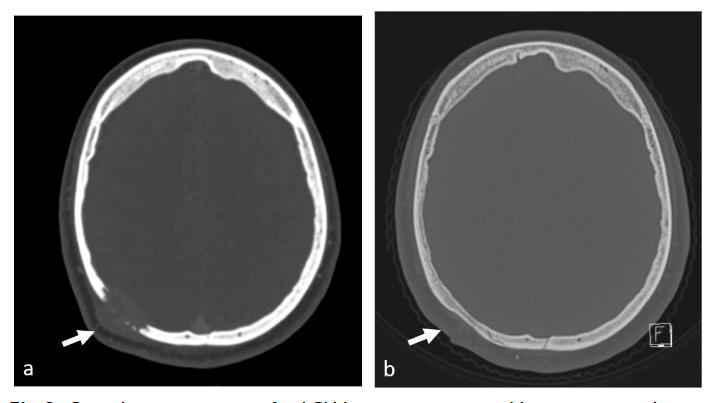

REGRESSION OF LESIONS

Regression of lesions occurred in 4 cases. In 2 cases regression was spontaneous, one lesion regressed completely and the second decreased in size while the patient awaited surgery, yet it was nevertheless resected. Biopsy initiated complete regression in 2 cases, the first case post-surgical biopsy and the second post FNB. The FNB case was a temporal lesion with CNS risk, yet complete regression did not require further treatment and no recurrence was reported in 17 years of follow up.

Regression of lesions occurred in 4 patients (11%). Two spontaneously and 2 post biopsies. In one of these patients, the lesion was a temporal bone lesion, a CNS risk lesion, and yet since it regressed spontaneously post FNB the patient was not treated and is disease free in 17 years follow up. Previous studies have documented similar spontaneous remissions of LCH bone lesions, including those affecting the calvaria. Regression has also been noted following biopsy, suggesting that biopsy could stimulate healing. The triggers for Langerhans cell proliferation and the factors that inhibit this process remain unclear. One hypothesis suggests that spontaneous resolution occurs due to a breakdown in self-tolerance, leading to the activation of immune effector cells that target and kill proliferating cells. A similar mechanism has been proposed for halo nevus. Consequently, some authors advocate for a short observation period as part of the initial management strategy for solitary calvarial LCH lesions to avoid unnecessary surgical intervention. Haupt et al. observed that often in isolated bone lesions, simple curettage during the diagnostic biopsy resulted in healing, therefore further intervention may not be necessary.